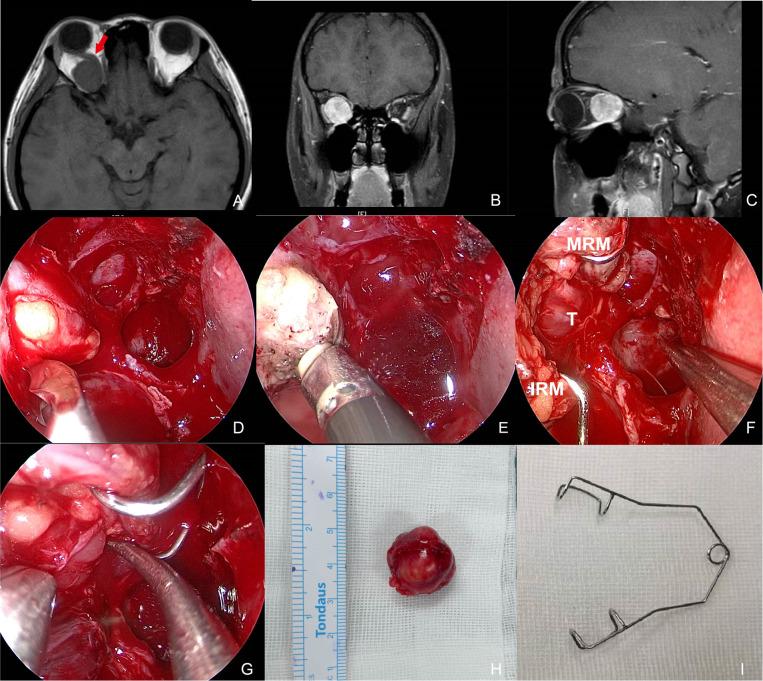

Four primary and one recurrent tumor were identified. The mean patient age was 50 (range, 29-64) years. One tumor was located lateral to the optic nerve, one central and three medial. A complete surgical resection was obtained in four primary cases and a partial resection was achieved in the recurrent case. The MRM was retracted using three different techniques: (1) an infant eyelid speculum creating an operative window between the medial and inferior rectus muscle, (2) external MRM disinsertion transconjunctivally, (3) a four-handed technique performed transseptally by two surgeons. Transient postoperative ophthalmoplegia was recorded in four cases and transient ptosis in one. Three patients completely recovered in 2-3 months while one undergoing MRM disinsertion ended up in restricted strabismus at 15-month follow-up. No other long-term complications have been noted in all five patients with a mean follow-up of 22 (range, 14-32) months. No patients with primary tumors have required additional surgery for tumor recurrence.

共发现4例原发性肿瘤和1例复发性肿瘤。患者平均年龄为50岁(范围29 - 64岁)。1例肿瘤位于视神经外侧,1例位于中央,3例位于内侧。4例原发性肿瘤实现了完整手术切除,复发性肿瘤实现了部分切除。采用三种不同技术牵拉MRM:(1)使用婴儿眼睑撑开器在鼻下直肌之间创建手术窗口;(2)经结膜外MRM断腱;(3)两名外科医生经鼻中隔采用四手操作技术。4例患者术后出现短暂性眼肌麻痹,1例出现短暂性上睑下垂。3例患者在2 - 3个月内完全恢复,1例接受MRM断腱术的患者在15个月随访时出现斜视受限。5例患者平均随访22个月(范围14 - 32个月),均未发现其他长期并发症。所有原发性肿瘤患者均未因肿瘤复发而需要再次手术。